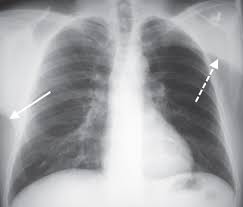

Abstract pneumothorax is the most urgent cause of a hyperlucent thorax. The radiographic finding that a lung or portion thereof is less dense than normal as from air trapping by a bronchial foreign body asymmetric emphysema or decreasing blood flow. Emphysema causes both over inflation and decreased pulmonary vasculature. Asymmetrical distance between the medial.

An x ray simply is fundamentally useless to properly diagnose your problem. A rotated posterior anterior view may result in artifactual decreased attenuation on the side rotated anteriorly because of a shorter distance between the patient and the incident x ray beam. Hyperlucency imaging a region on a plain film with tissue density allowing for transmission of x rays. Initial interpretation should include excluding pseudo causes of hyperlucency because of technical factors.

Spirometery of the patient was within normal limits. The most common causes of pulmonary hyperlucency in adults are summarized in figure 1. Hyperlucent lungs result from air trapping or decreased pulmonary vasculature. Unilateral hyperlucent lung.

Contrast enhanced computed tomograph cect of the chest showed an unremarkable lung fields and vasculature. An understanding of the broad differential di agnosis of pulmonary hyperlucency is necessary to determine the underlying cause and provide appropriate patient care. Every unnecessary x ray in a woman of child bearing age represents a danger that should be weighed against the benefits. What does lung hyperlucent mean.